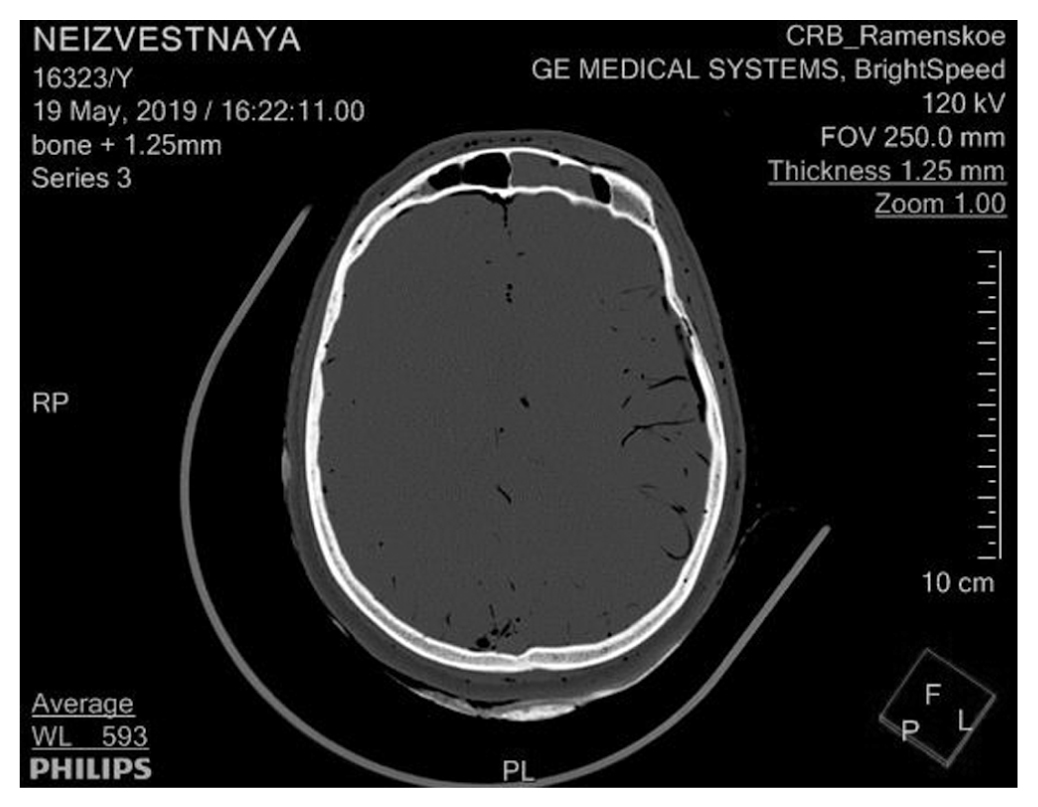

При компьютерной томографии трупа врачом-рентгенологом установлено: в обеих верхнечелюстных, основной и лобной пазухах, в отдельных клетках решетчатого лабиринта с обеих сторон определяется содержимое с горизонтальным уровнем жидкости, с наибольшим объемом жидкости в левой половине лобной пазухи (рис. 3, 4).

Рис. 3. Жидкость в лобной пазухе

Рис. 4. Жидкость в пазухах